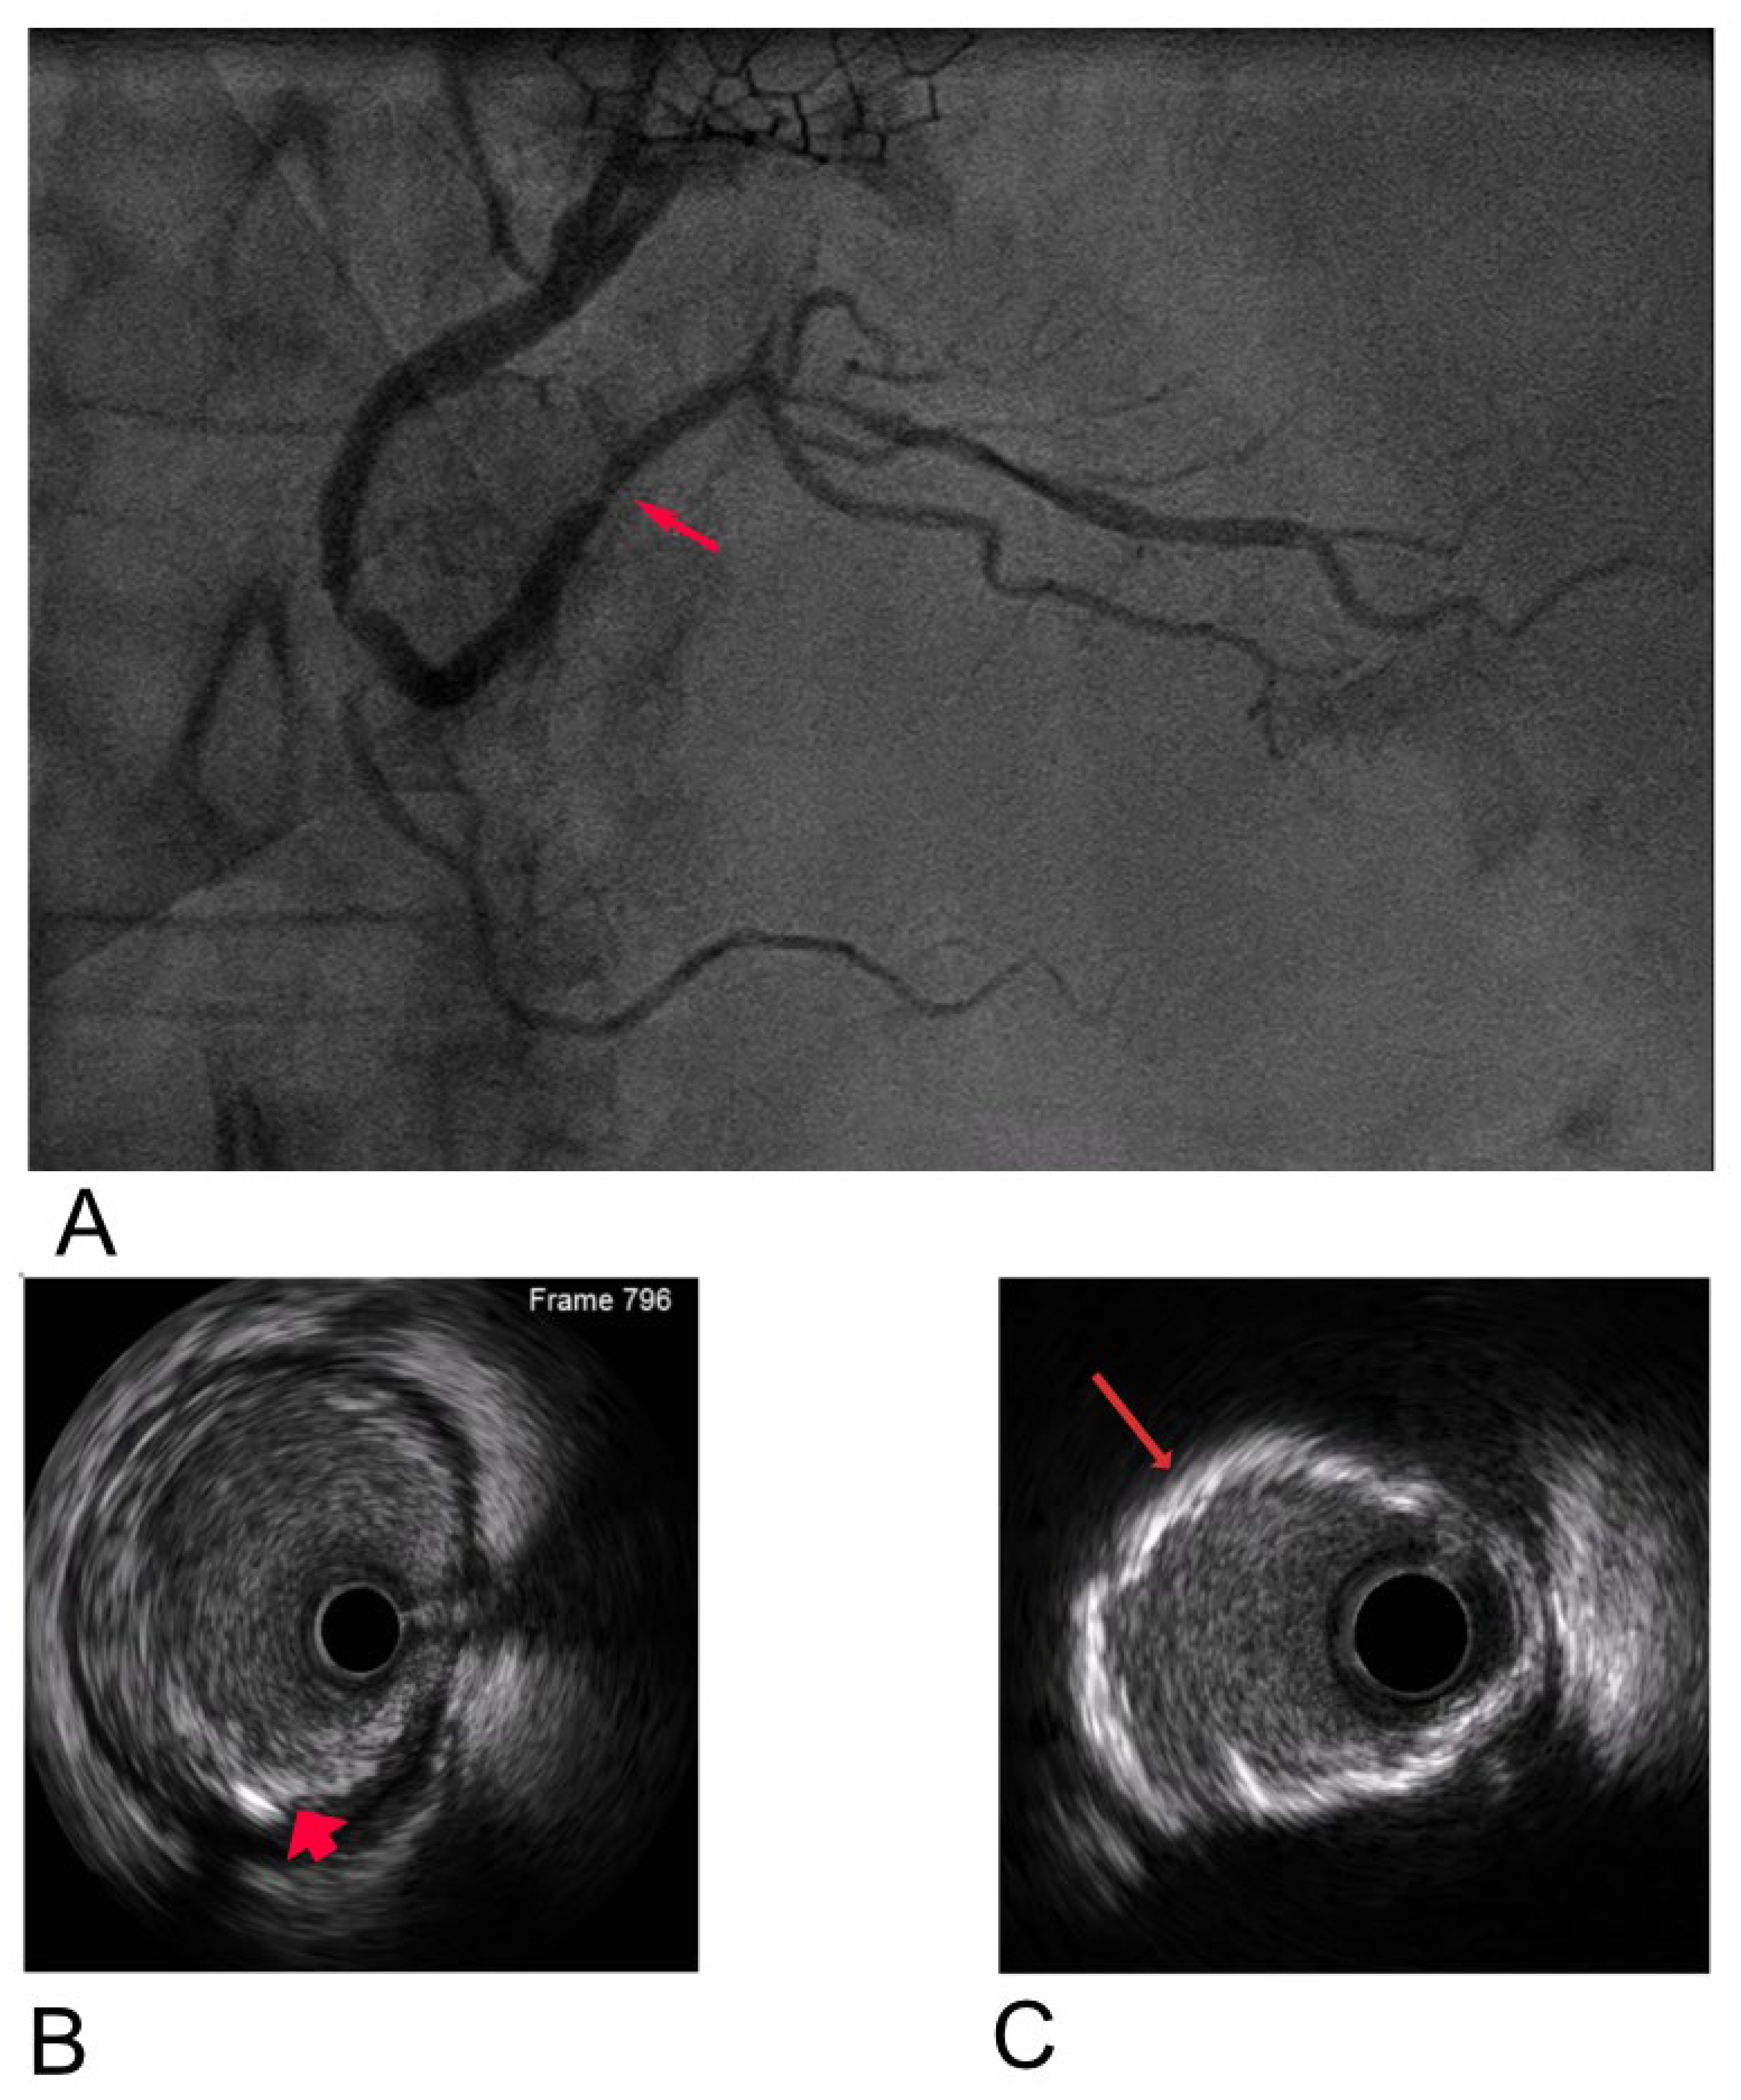

To address these challenges, adjunctive imaging modalities have been adapted to enable ultra-low contrast PCI. Intravascular ultrasound (IVUS) provides detailed cross-sectional images without reliance on contrast media (Figure 1) and is recommended in complex interventions [5,6]. OCT provides high-resolution plaque characterisation and stent assessment (Figure 2), but requires flushing, typically with contrast media; however, substitutes such as low-molecular-weight dextran and heparinised saline have shown promise as alternatives [51,52,53,54]. DCR software overlays a live coronary roadmap onto the fluoroscopic image, enabling navigation of coronary tools and stent delivery without repeated contrast injections (Figure 3) [7,55]. While these modalities provide valuable anatomical information, they remain dependent on fluoroscopic platforms and do not eliminate contrast use entirely, highlighting the potential role for complementary navigation technologies such as EAMS.

Figure 3. JL 3.5 coronary catheter (arrow) positioned in the left coronary cusp in LAO cranial view following coronary angiography (left). DCR map visualising the coronary tree without contrast injection (right).